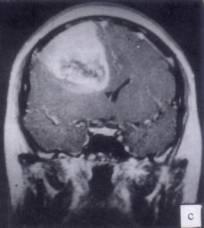

病历摘要:??患者男性,52岁。头痛伴呕吐2月,呕吐呈喷射性。既往身体健康。体检:神清,表情淡漠,反应迟钝,双眼底视神经乳头明显水肿,左鼻唇沟稍浅,左腹壁...

问题 病历摘要:??患者男性,52岁。头痛伴呕吐2月,呕吐呈喷射性。既往身体健康。体检:神清,表情淡漠,反应迟钝,双眼底视神经乳头明显水肿,左鼻唇沟稍浅,左腹壁反射减弱,左上下肢肌力4级,左Babinski征(-)。 术前的检查和治疗应包括下列哪些??提示:初步诊断考虑胶质瘤,拟手术治疗